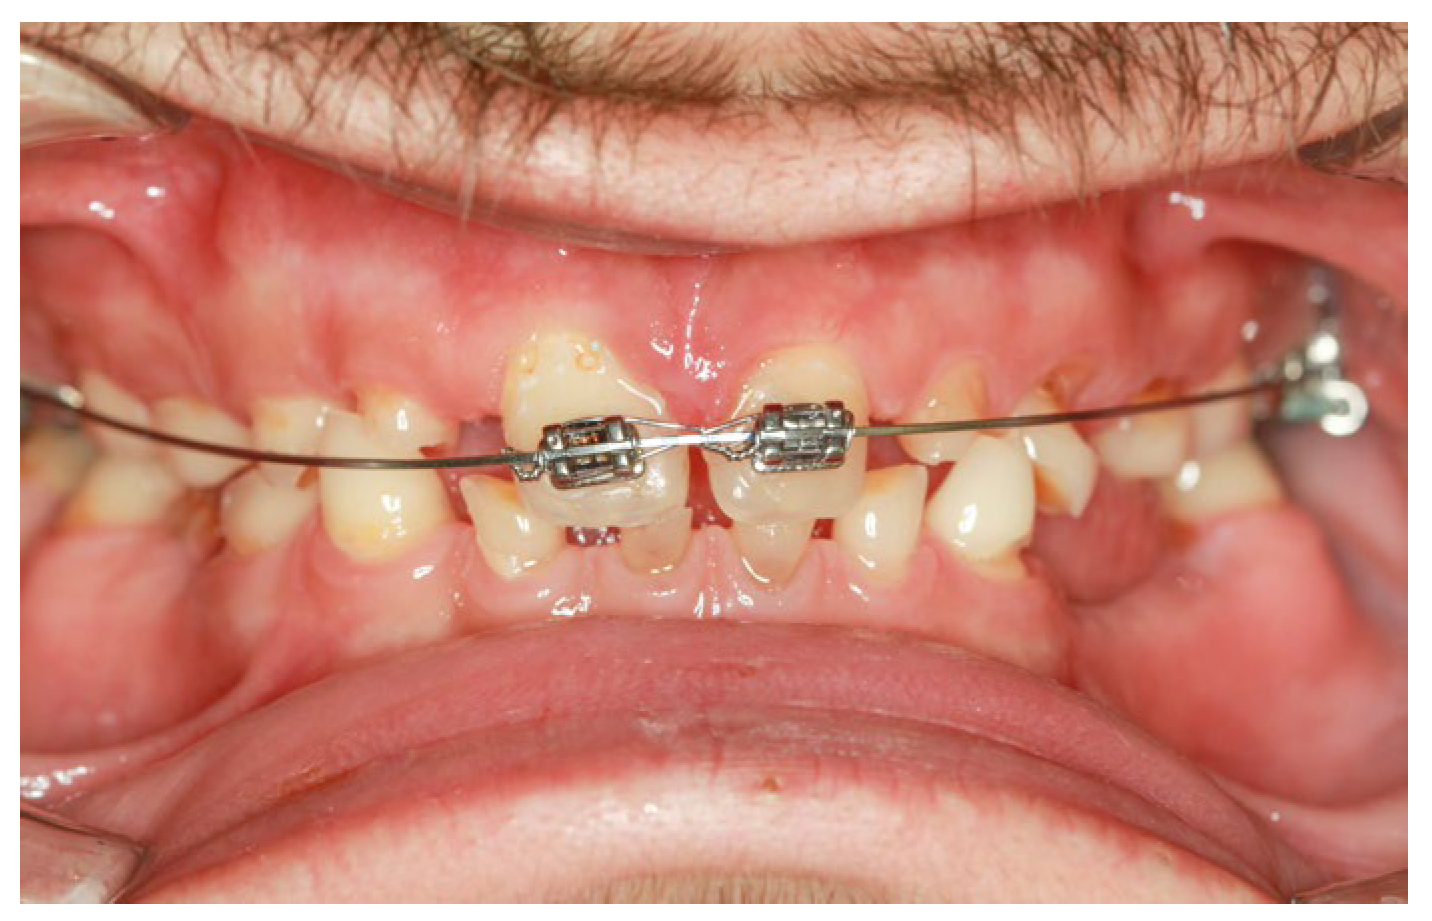

Figure 6.

Intraoral clinical aspect during the orthodontic treatment.

Preprosthetic orthodontic treatment was conducted with a partial fixed appliance (transpalatal bar and 0.022-inch Roth prescription brackets on the 11 and 21). The main objective of this treatment phase was to reduce the diastema and slightly retrude the upper incisor to improve the dental position for the final restorations (Figure 6).